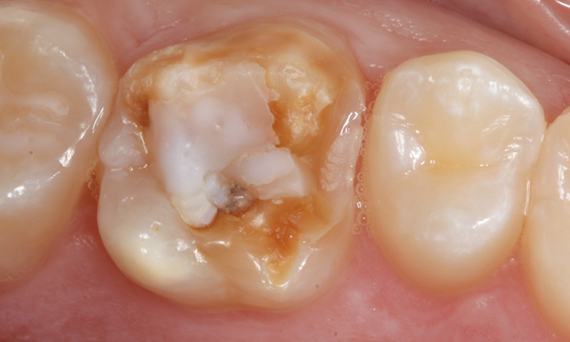

First upper molar, in 100 minutes

A CEREC Tessera inlay

The chairside restoration in a single visit proved to be a particularly effective and comfortable solution for this patient, as her commute to the practice was 50 kilometers. A highly esthetic inlay with CEREC Tessera could be realized.

Before: Fractured ceramic restoration made from a leucite-reinforced glass-ceramic after a clinical service time of 12 years.

After: Chairside-fabricated restoration made from an advanced lithium-disilicate ceramic CEREC Tessera.